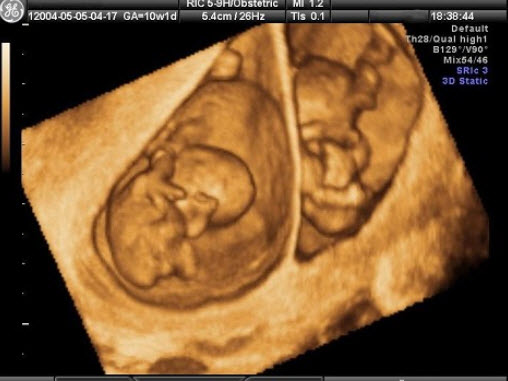

145、判断题

根据三维超声所见,图中为双胎妊娠。